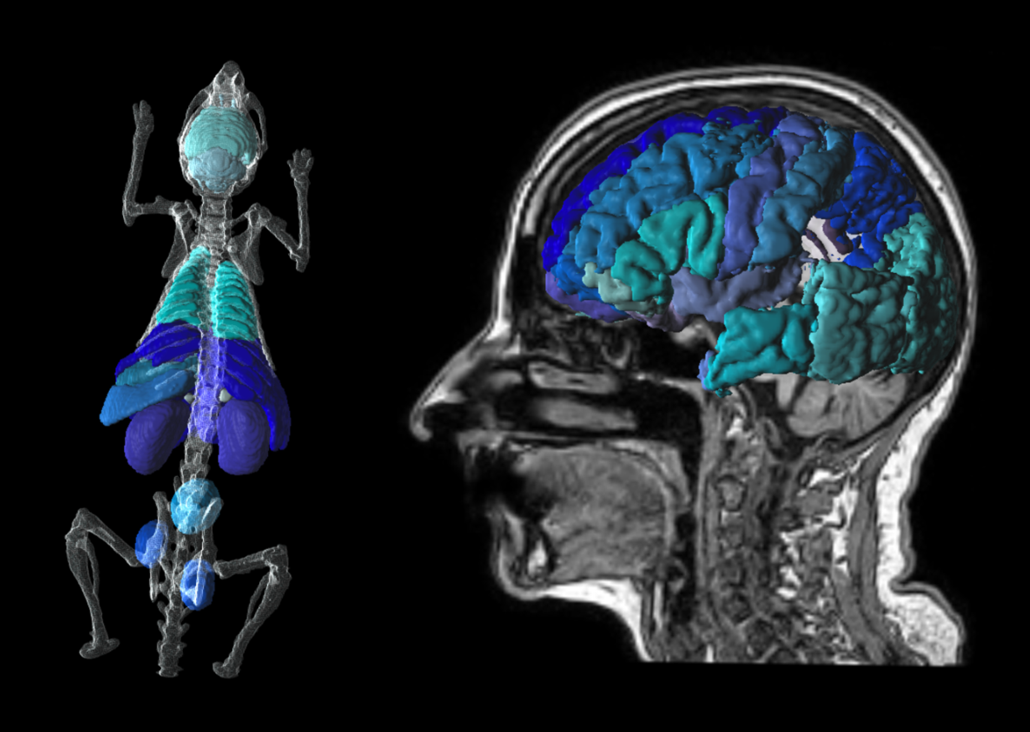

Czytaj więcejPNROD Rodent Brain Analysis

PNEURO Human Brain Analysis

This tool for the analysis of PET, MR and PET/MR brain images enables workflow-based brain atlases for humans, primates and pigs.

AI-based segmentation of deep nuclei with PAI.

PET partial-volume correction, and direct connection to parametric mapping.

Supports batch processing.

Recommended in combination with PKIN, PXMOD, PAI, PFUS, P3D